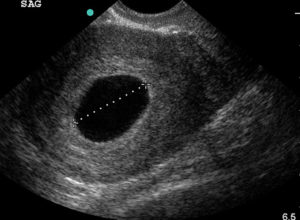

Доктор фиксирует на экране плодное яйцо — как выглядит оно, какие размеры имеет — и отмечает отсутствие эмбриона.

Если женщина сомневается в компетентности врача, то может пройти повторное обследование через несколько дней. При этом необходимо учитывать интенсивность выделений и исключить кровотечение. Если и повторная диагностика показывает плодное яйцо без эмбриона пустого кольца при этом видно на экране — то сомнения в предположении анэмбрионии нет.

Так на УЗИ выглядит пустое плодное яйцо.

Узи диагностика

Только на шестой неделе беременности пустое плодное яйцо можно диагностировать с помощью УЗИ. Оно проводится в любом случае, чтобы определить месторасположение плода, а также исключить внематочную беременность.

Определить анэмбрионию по УЗИ можно не ранее 5-6 недель беременности, но и на этом сроке могут быть ошибки.

Диагностических критериев для идентификации анэмбрионии довольно немного. Достоверным признаком отсутствия развивающегося эмбриона в плодном яйце является визуализация при помощи ультразвукового исследования.

Конечно же, бывают случаи, что беременность в плодном яйце есть, но не видно эмбриона. Эта ситуация относится к малым срокам.

Однако, если нет эмбриона в плодном яйце 6 недель или нет эмбриона в плодном яйце 7 недель, то тут стоит говорить о патологии.

Явным признаком неблагоприятного развития беременности, которые указывают на такую патологию, как анэмбриония, является отсутствие желточного мешка при размере плодного яйца 18,25 мм, а при его размере свыше данных показателей — отсутствия самого эмбриона. Если плодное яйцо 5 недель, то эмбриона не видно, но если нет эмбриона в плодном яйце 8 недель, то в этом случае можно смело говорить о наличии такой патологии. Предположить о неразвивающейся беременности можно косвенно по значениям уровня хорионического гонадотропина человека. Конечно же, ХГЧ будет иметь тенденцию к росту. Этим и отличаются анэмбриония и замершая беременность, при которой уровень ХГЧ будет стремительно падать вниз.

Согласно данных УЗИ, выделяют два типа анэмбрионии. Первый характеризуется тем, что диаметр плодного яйца не превышает 25 мм, размеры матки соответствуют 5–7 неделе беременности, но отстают от реального срока. При втором типе яйцо растет с нормальной скоростью и к 2,5 месяцам достигает 50 мм, однако не визуализируется ворсинчатый хорион.